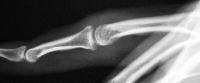

Case 3. 21 year old woman with pain developing in a congenitally angulated thumb.

Radiographs show a juxtaarticular ossification with  subchondral cyst formation of the bone interface with the lateral phalangeal head and lateral angulation of the proximal phalanx articular surface.